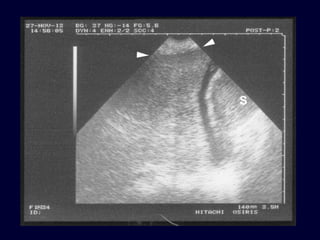

Tissue pattern representativeof Alveolar Consolidation Presence of hyperechoic punctiform images Presence of hyperechoic punctiform imagesrepresentative of air bronchogramsrepresentative of air bronchograms Pleural effusion Lower lobe

• 93.